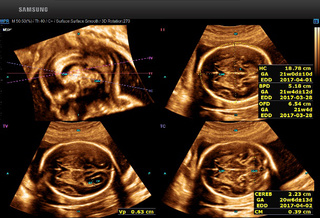

排畸神器 硬核设备!宜宾市首台5D智能彩超在翠屏区妇幼保健院 投入使用

什么是5D智能超声?

从一维的A超,到二维的B超,到三维3D超声,再到四维4D超声,超声技术得到了飞速发展。

近几年,随着AI人工智能科技的进步,带我们走向全新世界。三星5D智能超声,就是基于其领先的四维超声成像技术,搭载AI人工智能诊断技术这一新的维度,成为旗舰级5D智能超声系统。

5D超声能够全方位、多角度评估胎儿生长发育情况,广泛应用于胎儿染色体异常所致畸形(NT测量)、胎儿长骨畸形、胎儿心脏畸形、胎儿中枢神经系统畸形等产前筛查的各个领域。

5D智能超声通过大样本的数据分析,智能识别胎儿产前筛查所需多种标准切面,自动进行多项数据测量。对胎儿畸形的早期诊断提供比传统四维彩超更精确的数据!

↓↓胎儿颈项透明层智能识别分析技术 ↓↓胎儿颅脑智能识别分析技术

超高细微分辨率的图像质量以及超高灵敏度的低速血流检测能力,能够全方位的分析并提高病变检出率,通过全球领先的智能分析和诊断技术,显著提高了诊断准确率,孕期病变检出率提高到98%,并大大降低了误诊和漏诊率。

l 一般而言5D智能超声的最佳检查时间是22-26周 ,这段时期检查,因为胎儿大小及羊水适中,在宫内活动空间较大,体表也比较丰满,有利于胎儿成像和畸形筛查。